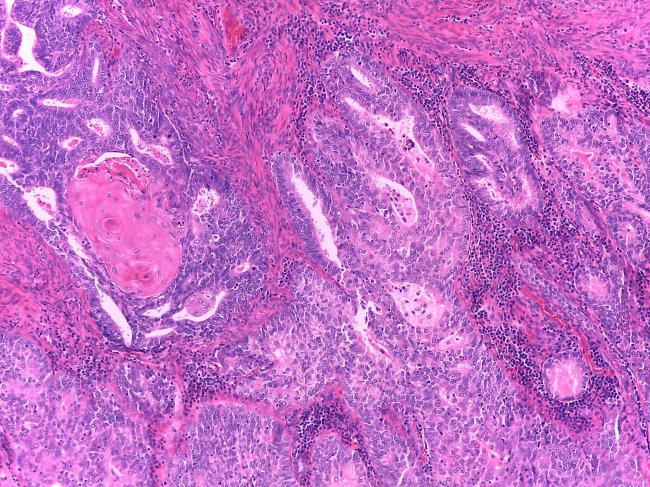

• Anatomia Patológica

Cancro do Endométrio

Cancro do colo do Útero

Cancro do Ovário